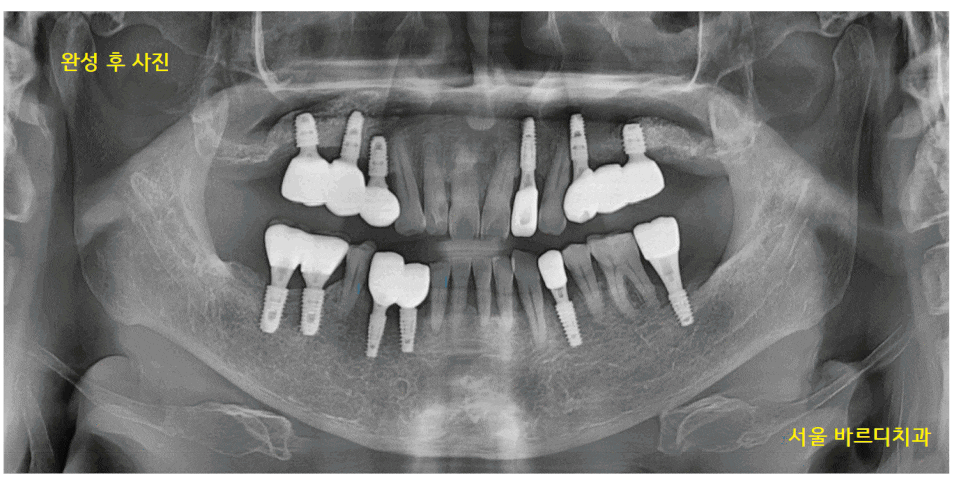

24.01.22

하남시청치과 치료 완료 후 사진입니다.

마음고생을 하셨던 환자분

이제 관리 잘 하셔서

오래오래 쓰실 수 있게 도와드리겠습니다.